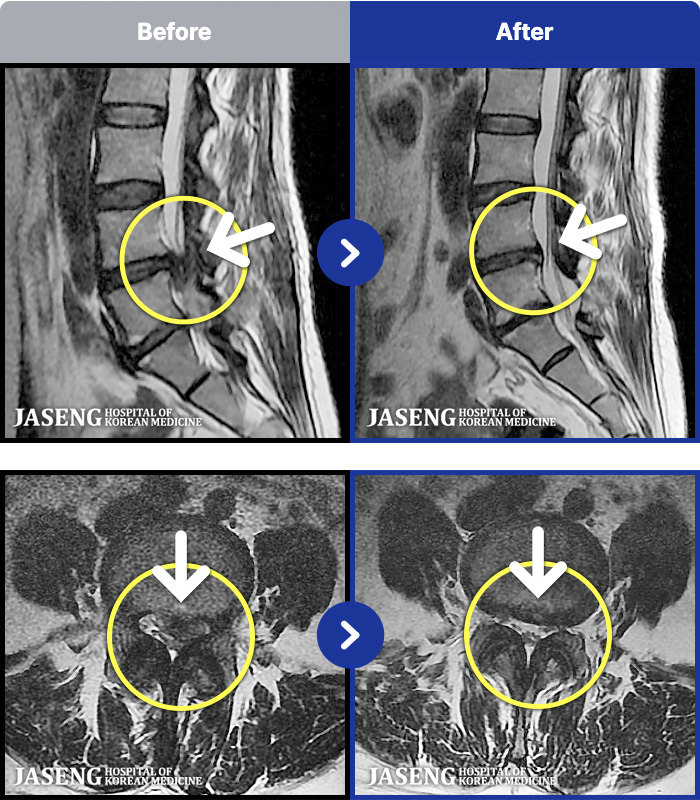

MRI ġ

1,240 MRI ũ ʸ Ȯϼ.

㸮 ϻ .